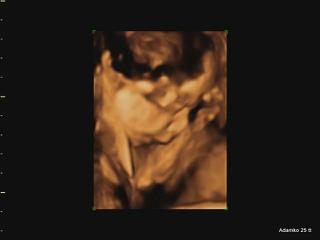

@adikad už som pozerala tvoje fotky v albume, je naozaj krásny 🙂 a ako jasne a zreteľne je vidno tváričku!